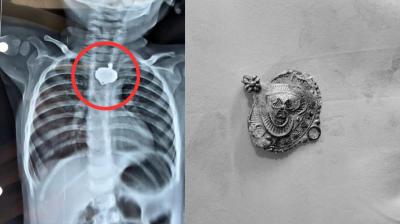

बड़वानी में 9 माह के बच्चे की आहार नली में फंसा मंगलसूत्र, डेढ़ महीने बाद एक्स-रे से खुलासा

24 Nov, 2025 08:30 AM IST | MP03.IN

बड़वानी: रविवार को जिला अस्पताल में एक बेहद संवेदनशील और हैरान करने वाला मामला सामने आया. जब 9 माह के एक बच्चे के गले में मंगलसूत्र फंसा हुआ देखा गया. घटना...